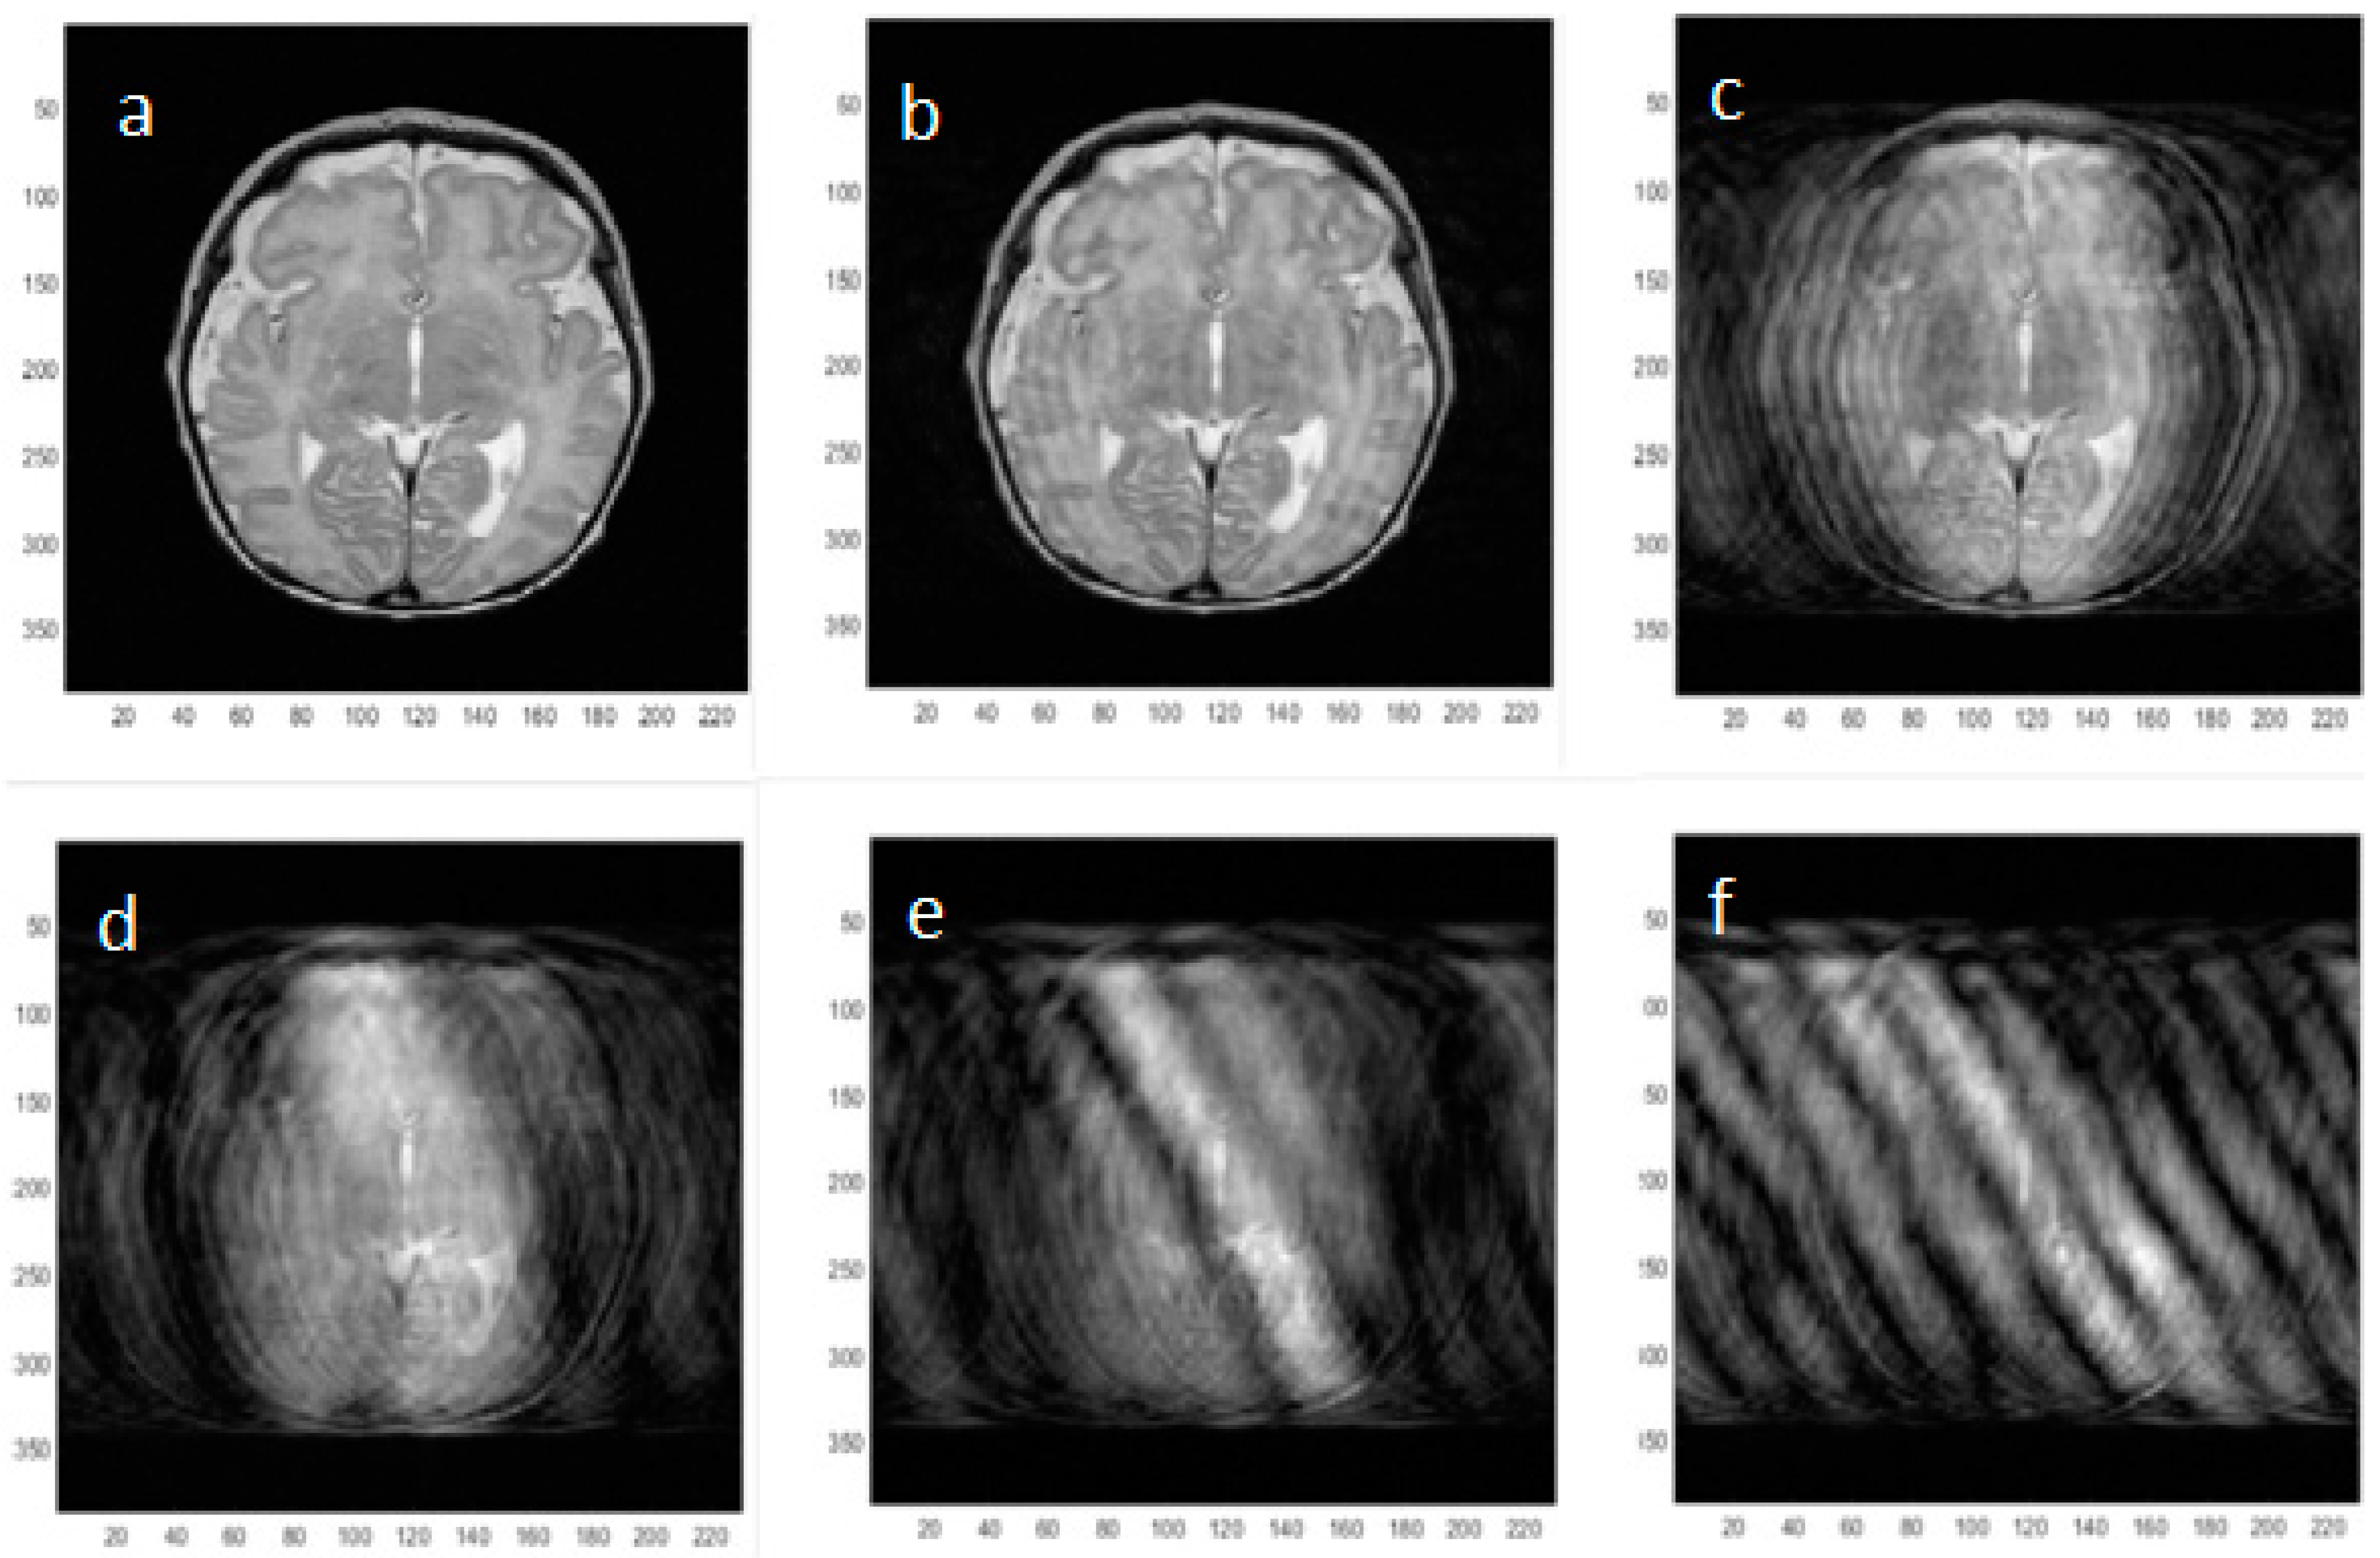

Images acquired with approximately five times more angular motion (2 × 10−1 radians), similar to the simulation shown in Figure 6e, are shown without and with motion in Figure 9a,b respectively and the result of the motion correction algorithm is shown in Figure 9c. The effects of the correction on the original k-space data are shown in Figure 9d–f. It can be seen that several offset k-space lines have been reassigned after the correction, although the overall correction still shows considerable artifact.

The red arrow on Figure 9c illustrates improved left edge definition produced by the correction. The large spikes offset from the center of k-space by motion seen in Figure 9e are removed by the correction algorithm as shown in Figure 9f but serious phase errors still remain in the data set causing residual ghosting.

Figure 6. Simulated neonatal axial MR images incorporating increasing amounts of in-plane pseudo-sinusoidal angular motion (alpha) as shown in Figure 5. The original image with no motion artifact is shown in (a) and then the peak-to-peak angular motion applied to the k-space locations is doubled in successive images (b) 2 × 10−2; (c) 4 × 10−2; (d) 8 × 10−2; (e) 1.6 × 10−1; (f) 3.2 × 10−1 radians to simulate neonatal head motion. A standard rotation matrix was used to multiply the k-space locations by the relevant measured angle. In principle, reversal of the motion effects by counter-rotating the k-space data according to the measured rotation angles should be possible.

Figure 9. MR images with no in-plane angular motion (a); and pseudo-sinusoidal motion (b); In (c), an attempt to remove the motion using the measured angles shows some improvement of the k-space data as can be seen by comparing (df) where the individual k-space lines are plotted together.